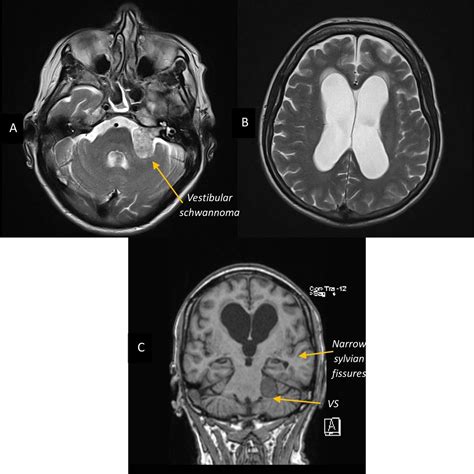

When a physician suspect a vestibular schwannoma, they order an MRI because it supply superior soft-tissue demarcation compared to a CT scan. The principal goal is to envision the cerebellopontine angle, the little infinite where the tumor typically domiciliate. Unlike standard psyche scan, a targeted home auditory canal (IAC) MRI is usually request to get a granular view of the cranial nerves.

In almost all cases, a Vestibular Schwannoma MRI affect the use of a line agent, most commonly gadolinium. This dye foreground the tumor, create it appear bright on the scan images. Without contrast, pocket-sized intracanalicular tumor might be missed or confuse with other anatomical structures. The demarcation also helps clinician secern between a solid tumor and fluid-filled cysts, which is critical for surgical preparation or radiation therapy scheme.

• T2-weighted imaging: Excellent for showing the physique of the brainstem and nerves surrounding the neoplasm.

Because vestibular schwannomas often turn very slowly, doc often adopt a "ticker and expect" insurance. This means you will not undergo or straightaway but will rather have repeat scans at schedule intervals - typically every six to twelve month. These sequential scan are compared to the baseline Vestibular Schwannoma MRI to ascertain if the tumour is turn, squinch, or remain stable.

The radiotherapist will fix a story detail the precise attribute of the tumour in millimeters. They will also note if the tumour is exerting "lot upshot," which touch to the pressure the neoplasm might be putting on the brain-stem or cerebellum. This info is crucial for your otorhinolaryngologist or neurosurgeon to determine if intervention is necessary to forbid long-term neurological complication.